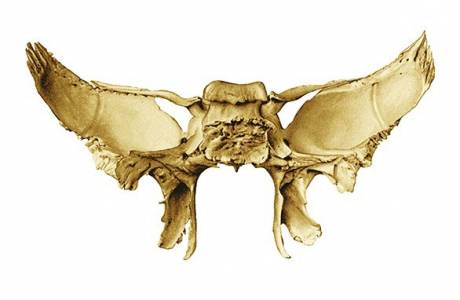

Los segmentos derecho e izquierdo en ambos lados están unidos al sacro, estructuralmente tienen la parte superior redondeada. La parte inferior está notablemente engrosada y acortada, y en medicina se llama cuerpo del hueso ileal, que junto con los elementos púbico y ciático forman la parte superior del acetábulo. El fémur y el sacro están unidos al cuerpo.

En la parte superior del hueso del ilion hay una expansión, que solo forma el ala del ilion. Esta es una estructura más frágil. Su borde curvo externo se llama cresta ilíaca, tiene la forma de una protuberancia y debajo está la muesca ciática.La parte cóncava del ala forma la fosa ilíaca, la convexa forma la superficie de los glúteos, y en la región posterior en el interior está el sitio articular del sacro y el hueso pélvico, que se llama superficie en forma de oreja.

Para la recolección de material biológico, se utiliza una aguja delgada con un diámetro de hasta 3 mm, que al final tiene una forma espiral, que permite cortar el tejido óseo. La punción se realiza en el área de la cresta ilíaca, desinfectada previamente con una composición de alcohol y yodo. El procedimiento se lleva a cabo bajo anestesia local, y los médicos específicamente para este propósito usan una solución de novocaína al 2%. Después de la recolección de material biológico, se puede formar un vacío, que pronto se restaurará debido a la regeneración de los tejidos dañados.